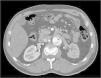

El 53.1% de los pacientes tuvieron antecedente de aneurisma aórtico; se encontró asociación significativa de aneurismas de aorta abdominal con los subtipos de DA según la clasificación de Stanford (p=0.047104). Así mismo, se encontró incidentalmente un caso con úlcera penetrante en el cayado en un paciente con aneurisma de aorta torácica con trombo mural asociado (fig. 6). La úlcera penetrante es, junto con la DA y el hematoma intramural, una de las patologías que componen el síndrome aórtico agudo, y consiste en la ulceración de placas ateroescleróticas que pueden llevar a hematoma intramural, disección o perforación aórtica15.